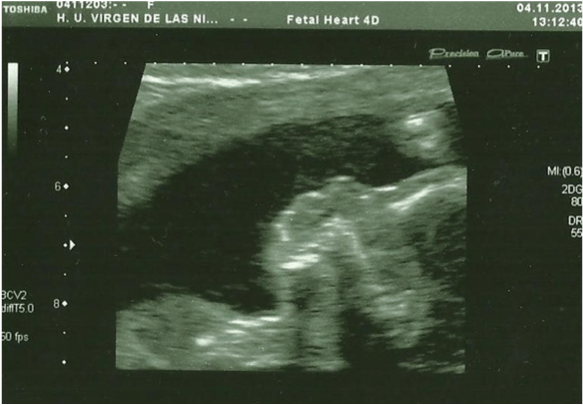

In the 20th week, a routine ultrasound, performed with an abdominal probe and ultrasound machine Toshiba Xsario X6, revealed a live fetus with biometry according to symmetric growth restriction (3rd centile for the gestational age) and estimated fetal weight, by Hadlock algorythm, of 201 grams. The ultrasound evaluation also showed a hypoplastic nasal bone (1.9mm) (Figure 1) without nuchal edema collapsed stomach and a single umbilical artery (Figure 2). Tricuspid regurgitation persisted and the fetal heart ultrasound was once again normal (Figure 3). Because of the risk of a genetic condition in the fetus, an amniotic fluid study was offered to the patient, and amniocentesis was carried out.

Figure 1: In the 20th week, the ultrasound evaluation show a hypoplastic

nasal bone, measuring 1,9mm (abdominal probe, Toshiba Xsario X6).

Figure 3: Fetal heart ultrasound in the 20th week, Tricuspid regurgitation.